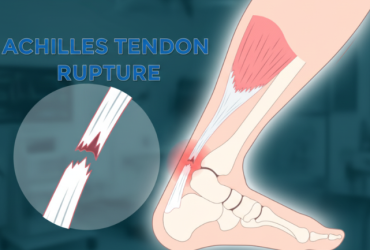

Achilles Tendon Rupture – a tear in the strongest tendon of the body, often caused by sudden movements or sports injuries.

Achilles Tendon Rupture

An Achilles tendon rupture is a tear of the tendon that connects the calf to the heel, often caused by...